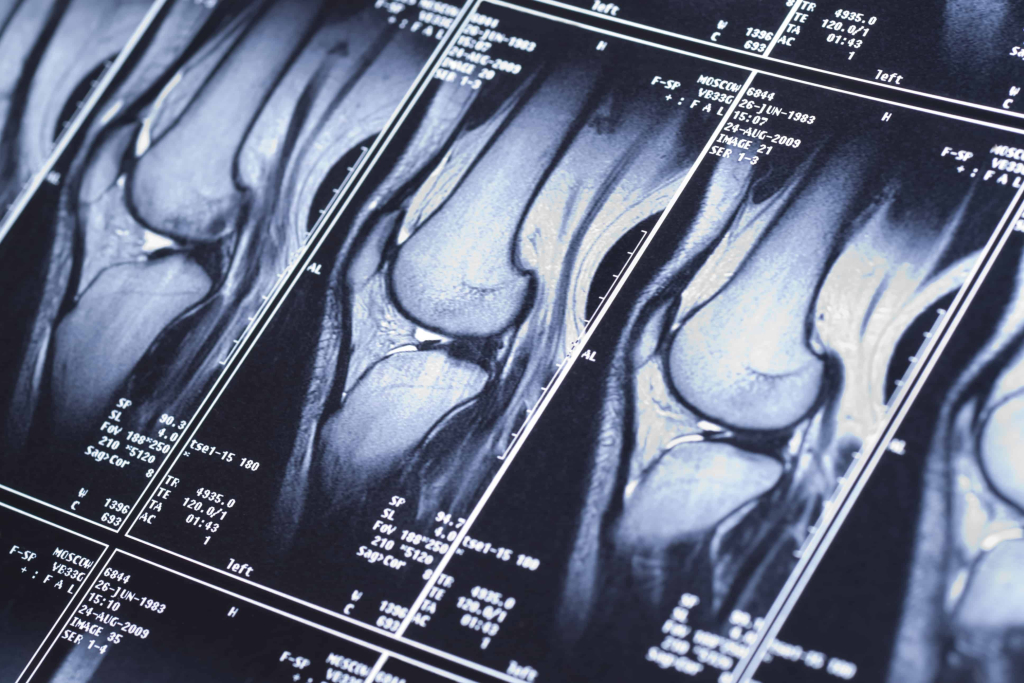

MRI

A magnetic resonance imaging (MRI) will be able to take pictures of cartilage and ligaments to determine if there is a meniscus tear. The MRI’s accuracy for diagnosing meniscus tears is 77 percent.

Sometimes, meniscus tears may not show up on an MRI because they can closely resemble degenerative or age-related changes. Additionally, some structures around the knee can closely resemble a meniscus tear therefore increasing the chances of a doctor making an incorrect diagnosis.